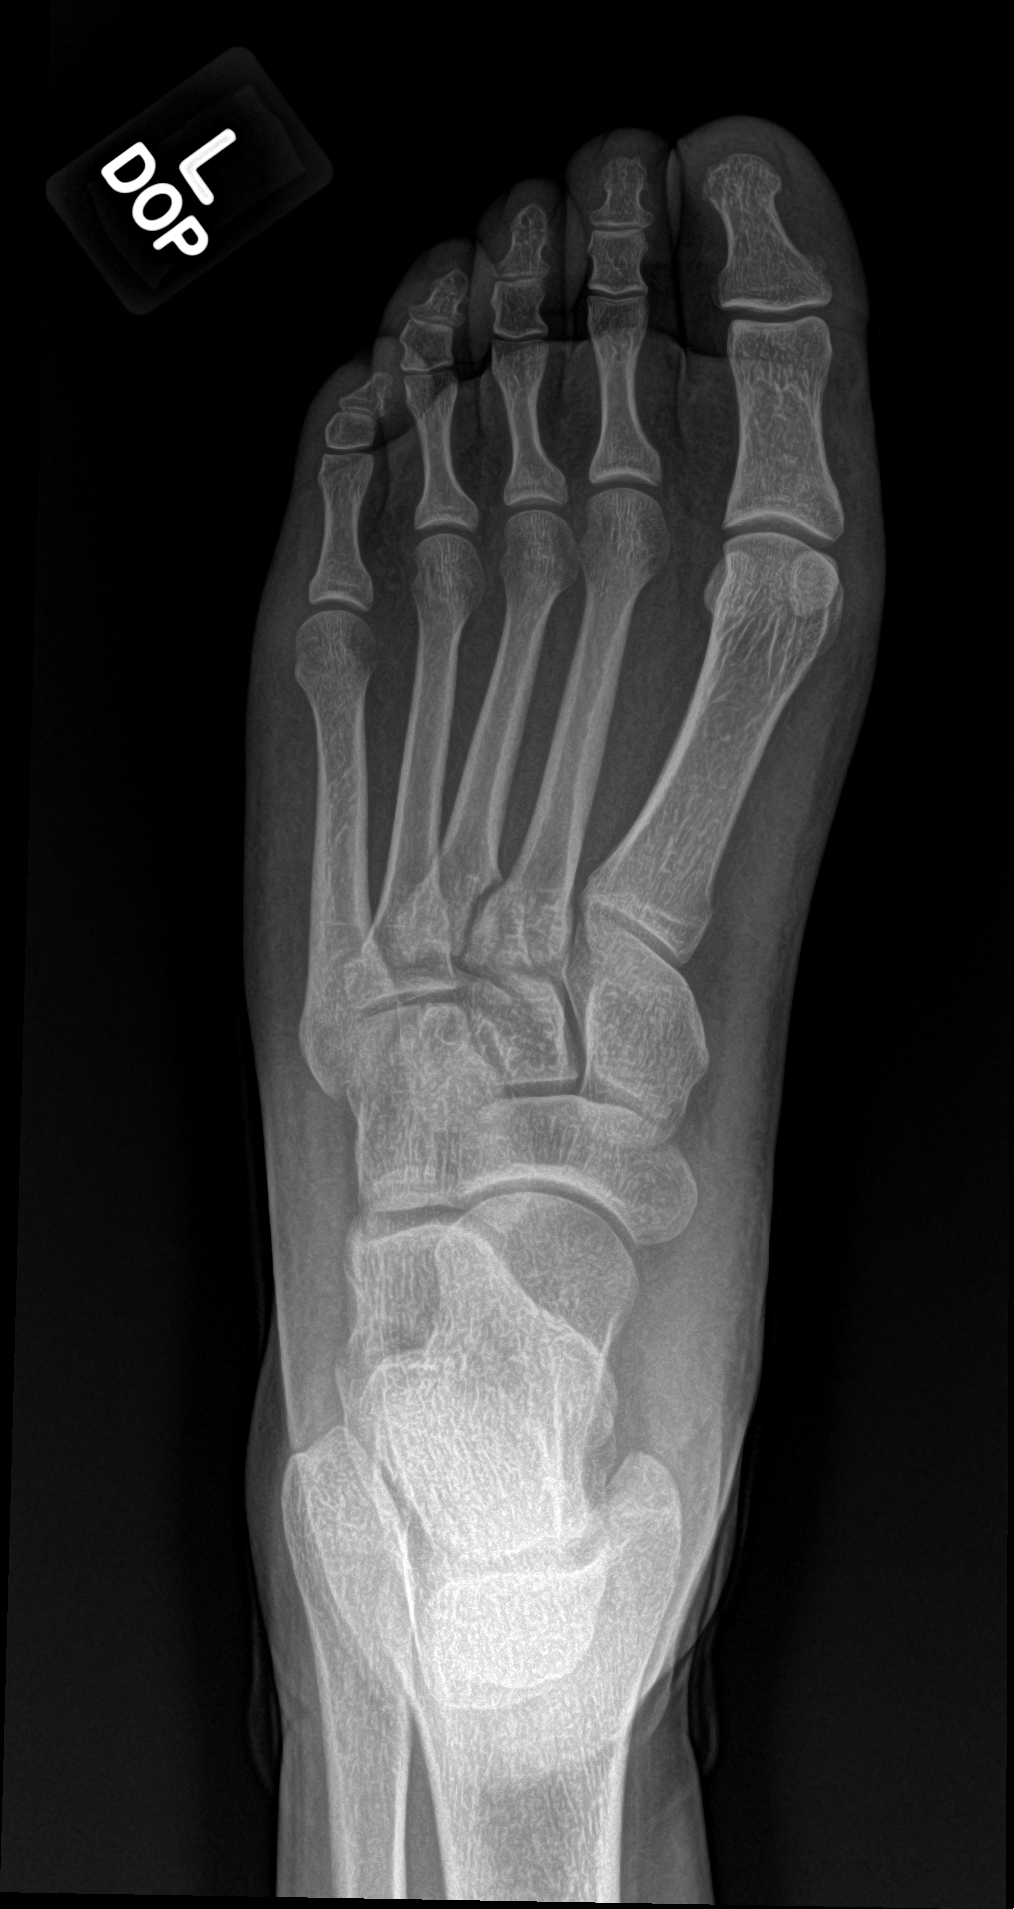

A 21 year old female with left forefoot pain after rolling her foot 2 weeks ago.

base of the 3rd metatarsal fracture